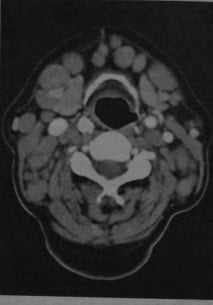

Лимфома шеи у женщины с хроническим лимфолейкозом. КТ с контрастированием: выраженное увеличение размеров и количества шейных лимфатических узлов, особенно в переднем и боковом треугольниках шеи. Плотность лимфатических узлов соответствует окружающим мышцам или выше.

Неходжкинская лимфома. КТ с контрастированием: множественные лимфатические узлы под нижней челюстью и около яремной вены, а также позади грудино-ключично-сосцевидной мышцы. Узлы имеют овальную или округлую форму, повышенную плотность по сравнению с окружающими мышцами, после введения контраста наблюдается гомогенное усиление.